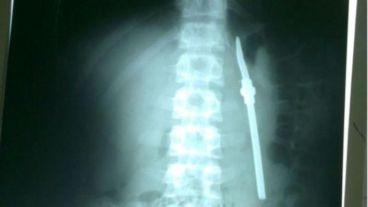

Según apuntó Minutouno, el delincuente fue preso acusado por robo y tentativa de homicidio. Tras ingerir el sorbete metálico fue derivado al Hospital San Martín, donde se le detectó el elemento.

El ladrón fue operado y se le sacó la bombilla. El parte médico indicó que su evolución es favorable y que podría volver a la cárcel en cuestión de días.